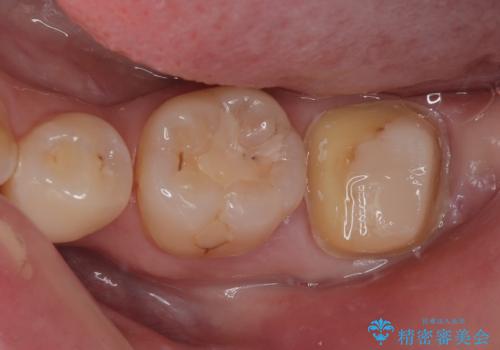

- 左下の奥歯が欠けたとのことで来院された患者様です。検査の結果、埋まっている親知らず抜歯とその手前の左下の7番目の歯のフルジルコニアクラウンによる補綴治療をおこなっていくこととしました。

左下の虫歯が大きいため、神経のテストも行いましたが正常な反応を示しました。